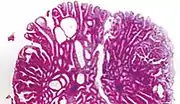

TypeRisk of containing cancer cellsHistopathologyImage

Hyperplastic polyp 0% No dysplasia.[13]

• Mucin-rich type: Serrated (“saw tooth”) appearance, containing glands with star-shaped lumina.[14] Crypts that are elongated but straight, narrow and hyperchromatic at the base. All crypts reach to the muscularis mucosae.[14]

• Goblet cell-rich type: Elongated, fat crypts and little to no serration. Filled with goblet cells, extending to surface, which commonly has a tufted appearance.[14]

Tubular adenoma 2% at 1.5cm[15] Low to high grade dysplasia[16] Over 75% of volume has tubular appearance.[17]

Tubulovillous adenoma 20% to 25%[18] 25%-75% villous[17]

Villous adenoma 15%[19] to 40%[18] Over 75% villous[17]

Sessile serrated adenoma (SSA)[20]

• Basal dilation of the crypts

• Basal crypt serration

• Crypts that run horizontal to the basement membrane (horizontal crypts)

• Crypt branching.

Colorectal adenocarcinoma 100%

• In carcinoma in situ (Tis): cancer cells invading into the lamina propria, and may involve but not penetrate the muscularis mucosae. Can be classified as "high-grade dysplasia", because prognosis and management are essentially the same.[13]

• Invasive adenocarcinoma: Extending through the muscularis mucosae into the submucosa and beyond.[13]